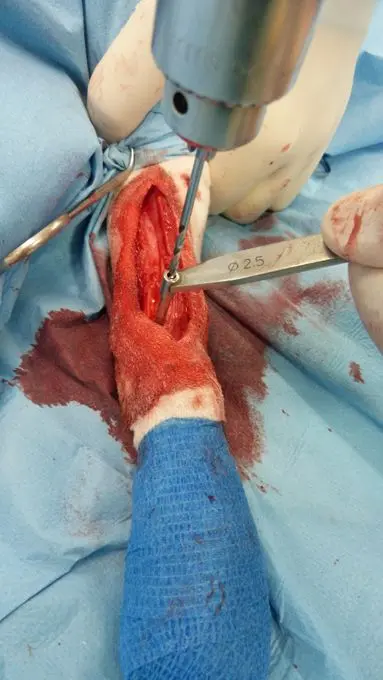

Técnica quirurgica

Perforación del hueso (aguja de 2.5 mm)

Colocamos 4 rótulas en la barra de distracción (no debe cortarse inicialmente ya que se forman “rebabas” que impiden enroscar las rótulas): 2 en la parte de giro a la dcha y 2 en la parte de giro a la izda. Perforamos un orificio en el fragmento distal del radio perpendicular al hueso y en la localización planificada (Fig. 5) . Si la aguja con rosca en la punta tiene el mismo diámetro que los pasamachos de los tornillos (2.0-2.7-3.5) podemos utilizarlos para labrar su rosca en el hueso (ello asegura menor osteolisis alrededor de los implantes).